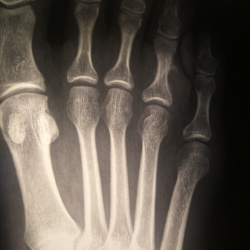

Всем доброго дня! Помогите, пожалуйста, разобраться. Пациент мужчина 59 лет. Направлен на рентгенографию стопы по поводу перелома основной фаланги 1 пальца. Образование в пяточной кости, по сути,...